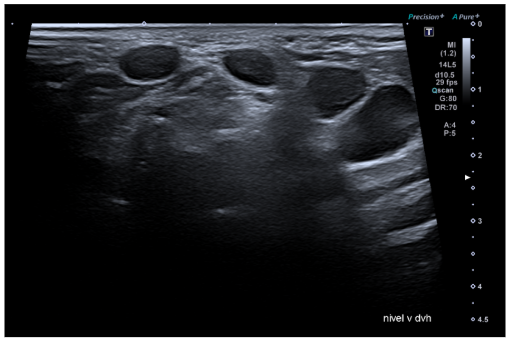

Hallazgos ecográficos

Ecografía clínica: adenopatías patológicas, sin grasa en su interior, redondas (no ovoides) de 1 cm de diámetro aproximadamente.